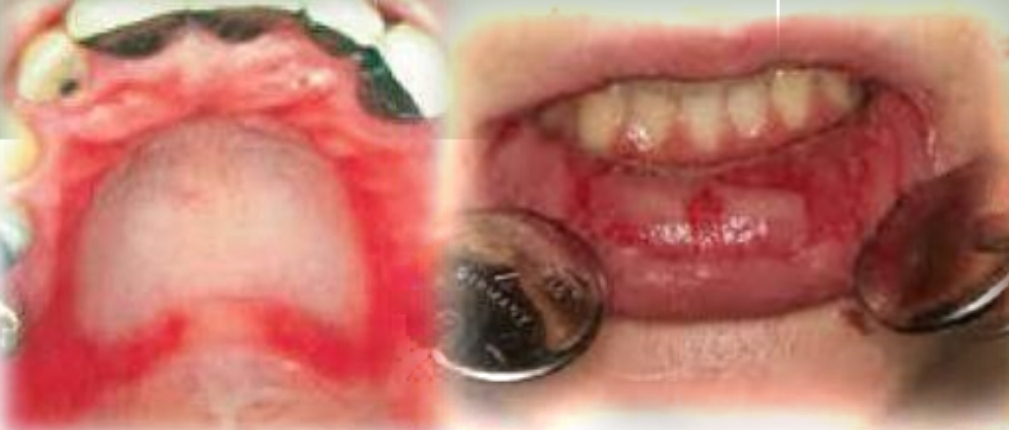

Multiple red macules to diffuse red patches

Depapillation of tongue

Burning sensation

Possible angular chelitis

First and second decades

No gender bias

Found on:

Palate, Buccal mucosa, dorsal tongue

Ask: medications, palatal coverage appliance, check medical history. In infant, use of pacifier?

Erythematous candidiasis

Candida albicans and other species

Contributing factors: Antibiotics, immunosupression, xerostomia, pacfier, palatal coverage appliance

Treatment - Antifungal medication and proper oral hygiene. May recur if cause not eliminated or managed

DD - Contact allergy, Traumatic erythema, Erythema migrans, Thermal burn, Anemia